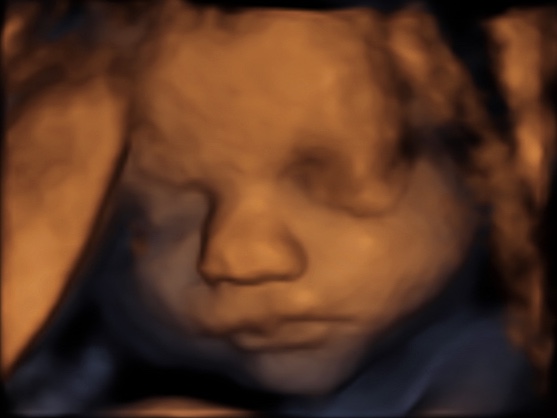

8 weken

12 weken

16 weken

21 weken

25 weken

30 weken

34 weken

37 weken

39 weken